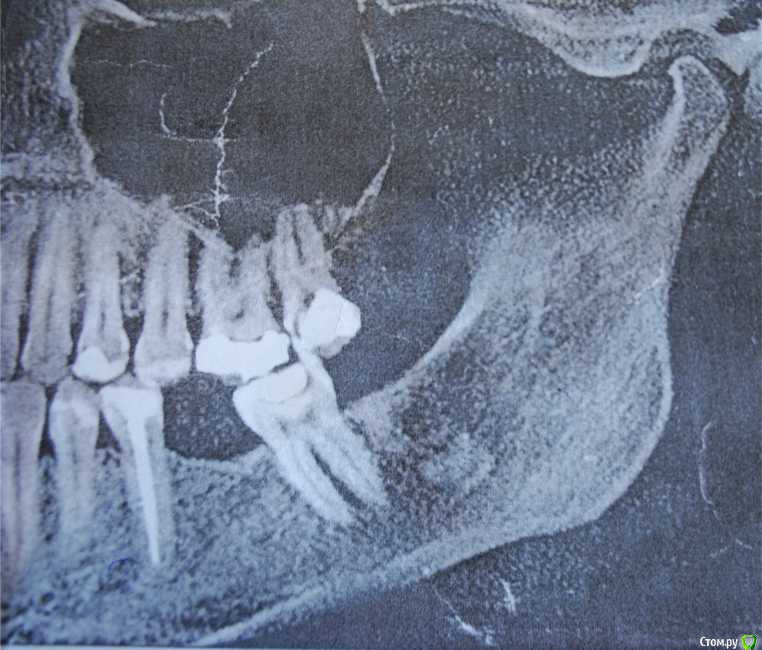

Лена35 Опубликовано 29 января, 2015 Поделиться Опубликовано 29 января, 2015 Уважаемые доктора, огромная просьба проконсультировать по поводу беспокоящей меня уже продолжительное время ситуации. С апреля 2013 года началось активное лечение зубов с эндодонтии на двух нижних передних зубах, пришлось и разрез сделать для удаления гноя. После этого сразу же появилось стойкое ощущение онемения губы и подбородка слева. Это ощущение есть до сих пор, иногда стало покидать, но возвращается, может по нескольку дней не быть. С тех пор было пролечено и депульпировано много зубов, потому что они стали болеть, но после всех депульпирований зубы продолжают также болеть по году. Нижние два передних болели 1,5 года и всетаки перестали болеть. Сейчас болят депульпированные верхние 5, 6 ,7 справа, нижняя 5 справа. Лечение было проведено качественно с микроскопом. После лечения в сентябре 2014 (4 месяца назад) 6 зуба справа был сделан в дешевой клинике 25летним доктором специальный укол для анестезии между челюстями, просили открывать рот до невозможности. После чего воспалился височно нижнечелюстной сустав справа, боли были острые в течение месяца. Было вправление вывиха. После чего маленькая дочка очень сильно ударила головой случайно в полуоткрытую челюсть слева и у меня распух внчс слева и появилась острая боль в суставе, режущая боль в ухе и боль жгучая в области выявившихся на томограмме инородных тел в области вырванного 10 лет назад зуба мудрости внизу слева. Все 10 лет меня этот зуб не беспокоил, изредка я ощущала небольшой дискомфорт там, как будто зуб растет и думала, что это фантомные боли. Они были кратковременные и не мешали мне жить. А вот с сентября боли в этом месте постоянные, изнуряющие. Я уже обошла нескольких многоуважаемых челюстно-лицевых хирургов в Новосибирске. 6 хирургов сообщили, что это либо остатки зуба, которые обызвествились, либо остеома, в обоих случаях беспокоить эти элементы не должны и в практике хирургов нет случаев острых болей из-за таких элементов. В это же время посетила профессора по внчс - диагноз - миофасцеальный болевой синдром и цементомы, которые не являются источником болей. Направлена на лечение к неврологу и ортопеду. На данном этапе прохожу пришлифовки суперконтактов, челюсть была не на месте из-за неправильного прикуса перекрестного, который случился из-за множественных пломб, не подогнанных под прикус - воспаление суставов могло из-за этого начаться. Далее диагноз - умеренный деформирующий артроз суставов. Прохожу лечение у невролога - просто принимаю препараты - пиакследин, артра, катадолон, курсами нвпс, мажу диклофенак, хондра. Во вторник установлю аква сплинт – для снятия мышечного напряжения, улучшения работы нейро-мышечного аппарата и снятия болевого синдрома. Все что меня беспокоит – это боль. Также пришлифовки у ортопеда и в перспективе фиксация прикуса коронками на жевательных зубах и поднятие прикуса. Забыла отметить, что 7 доктор по КТ сделал вывод, что инородные тела находятся в зоне нижнелуночкового нерва, могут вызывать компрессию и подлежат удалению. Но остальные 6 хирургов – кандидатов и докторов наук – выражают опасения, что при удалении нужно будет вырезать большой кусок челюсти, могут быть травмированы значительное количество нервных пучков и сам нижнелуночковый нерв и тройничный нерв и тогда мне станет намного хуже. Я очень боюсь такой операции, но постоянная боль в этой зоне изводит меня. Последний хирург сказал, что рядышком травмированы связки при вывихе, и это они дают туда эту боль. Десна в этом месте нормальная, гладкая, розовая, иногда в десне дискомфорт при жевании, но с этим можно жить. Боль в области элементов такая: жгучая, режущая, после катадолона или нвпс становится тупой. Важно – ночью – ничего не болит! Ни зубы, ни элементы, ни суставы! Как только начинаю говорить или двигать шеей – начинается боль, к обеду она сильная, к вечеру еще хуже. Нейростоматолог считает, что от множественных стоматологических вмешательств и длительного открывания рта произрастает боль и что в мозгу у меня уже сформировалась зацикленность и болевая доминанта, советует амитриптилин и ничего не удалять. Ведь пока я не знала об этих элементах – то и не болело там. А как узнала – сразу боль. Пью противотревожные - Стрезам, фенибут, персен. Как стала их пить – стало полегче – перестало пугать подергивание по линии тройничынх ветвей слева и отношение к проблеме стало более ровное. Конечно мое состояние тревоги и страха накопилось уже в нереальной степени, ведь я почти два года испытываю боли, сначала зубные, потом суставные и вот эти – в области элементов, которые меня страшно пугают из-за возможной операции, которая грозит невритом, параличом. Но испытывать такую боль всю оставшуюся жизнь я тоже не смогу. Очень важно ваше мнение – что мне делать – ждать, удалять эти элементы или думать, что боль идет от суставов и спазмированных мышц и лечить суставы. Мне очень морально тяжело, не сойти бы с ума. Может и правда пропить антидепрессанты. Но от них же не пройдет боль. Заранее благодарна за помощь. Прилагаю компьютерную томограмму. Ссылка на комментарий

Korel Опубликовано 29 января, 2015 Поделиться Опубликовано 29 января, 2015 С удалением остатка 38 никаких проблем не будет. Что касается образования, расположенного на уровне нижнечелюстного канала, нужны доп. исследования. Снимок не очень хорошего качества. Ссылка на комментарий

Alejandro Опубликовано 29 января, 2015 Поделиться Опубликовано 29 января, 2015 Соглашусь с коллегой: корень восьмёрки не проблемный, а вот что там у вас в области самого канала? Нужны более чёткие снимки... Ссылка на комментарий

Лена35 Опубликовано 30 января, 2015 Автор Поделиться Опубликовано 30 января, 2015 С удалением остатка 38 никаких проблем не будет. Что касается образования, расположенного на уровне нижнечелюстного канала, нужны доп. исследования. Снимок не очень хорошего качества.У меня несколько компьютерных томограмм в динамике. На всех это инородное тело выглядит именно так. Мнения разделились - или обызвествленные остатки зуба, либо остеомы, но они не растут. Лично я вижу, что это корень у десны и часть зуба у луночкового нерва. Что будет, если при удалении низко расположенного образования будет поврежден или перерезан нижнелуночковый нерв? Ссылка на комментарий

Korel Опубликовано 30 января, 2015 Поделиться Опубликовано 30 января, 2015 (изменено) У меня несколько компьютерных томограмм в динамике. Покажите их, если не трудно. Стоит ли удалить корень и посмотреть не пройдут ли онемение губ и подбородка, а нижний элемент оставить? Для начала нужно определиться с образованием ниже, а корень возможно удалить "по пути". Он один вряд ли будет давать такую клинику. Есть вероятность, что образование ниже также фрагмент 38, тогда особых проблем быть не должно. Изменено 30 января, 2015 пользователем Korel Ссылка на комментарий

Alejandro Опубликовано 31 января, 2015 Поделиться Опубликовано 31 января, 2015 Сделайте скриншоты из вашей 3д программы и залейте их в тему через радикал, вторая ссылка. Причём нужны скриншоты именно образования в области нижнечелюстного канала. Ссылка на комментарий